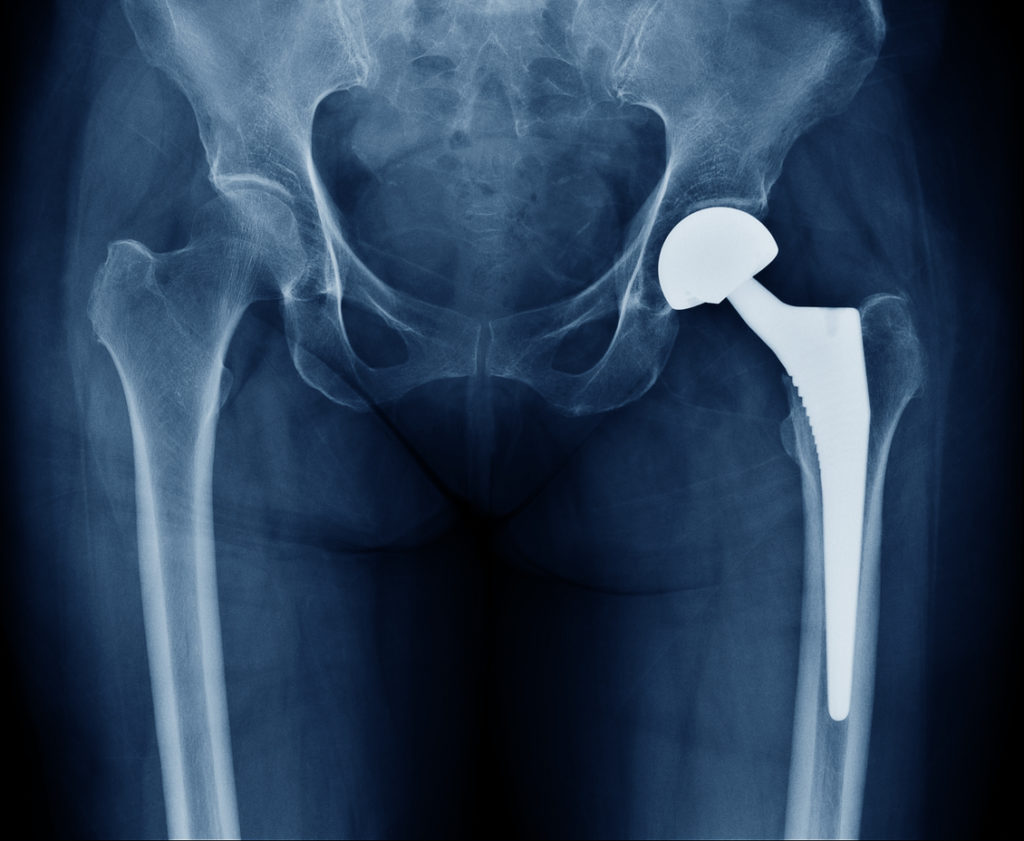

The most common orthopedic use for metal alloys is in prosthetics – including prosthetic hips and knee replacements. Metal alloys are also used in bone screws and bone plates.

Polymers help where other implant materials cannot. These materials are particularly useful in mimicking cartilage or ligaments that may have degenerated over time or after significant trauma. Total hip and joint replacements are just some of the instances in which a polymer can be used to adapt to the body’s tissue.